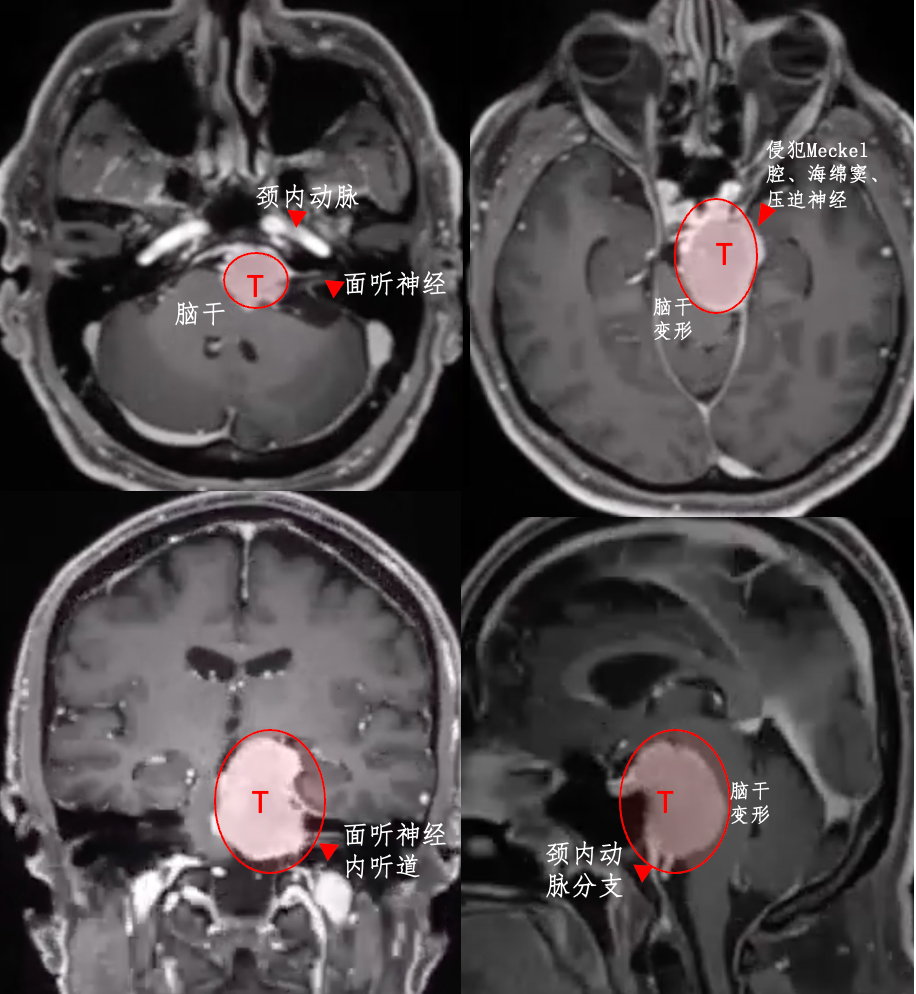

案例一:尺寸为29×39×38 mm的大型岩斜区脑膜瘤,肿瘤体积如小山丘状,顶部直接压迫"生命禁区"脑干,并与神经血管结构紧密粘连。患者初期仅表现为头痛症状。

需要明确的是,岩斜区脑膜瘤的大小每增加1cm,手术难度相应提升。鉴于肿瘤位置险要且体积较大,多数观点认为需通过开颅手术才能实现全切。然而,在INC福教授制定的个体化手术策略下,无需开颅,仅通过右侧单鼻孔入路便实现肿瘤全切。术后脑干复位良好,未出现脑脊液漏及新发神经功能障碍。

案例二:54岁男性Bruno,同样患有岩斜区脑膜瘤,但临床表现更为严重。患者出现左侧面部刀割样疼痛,伴随吞咽困难,导致无法进食、睡眠障碍及工作能力丧失。

为何症状如此严重?2014年确诊岩斜区脑膜瘤后,考虑到肿瘤属良性且手术风险,患者选择保守观察。然而经过6年时间,肿瘤持续生长压迫脑干,症状进行性加重。福教授采用开颅手术方案,术前通过线圈在咽升动脉处进行栓塞,显著减少术中出血。肿瘤切除过程中使用CUSA刀进行逐步减瘤。术后MRI显示肿瘤接近完全切除,脑干受压解除。